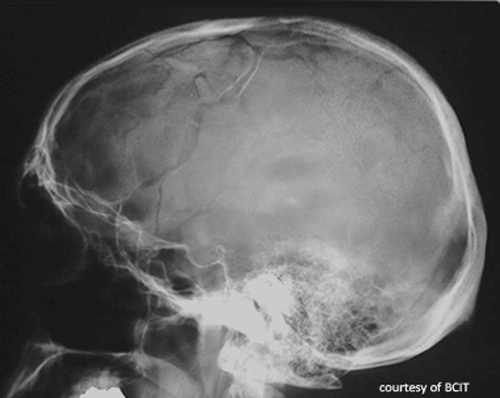

Skull radiography and CT help guide treatment and distinguish sutures or artery grooves from fracture lines.

Sutures (jagged, interlocking edges) and middle meningeal artery grooves (normal grooves that can mimic fractures on lateral views).

How can sutures be differentiated from fracture lines on imaging?

Sutures appear jagged and interlocking; fracture lines are linear, sharp, and may cross edges unnaturally.

It is a normal groove for the artery and can mimic fracture lines on lateral views.